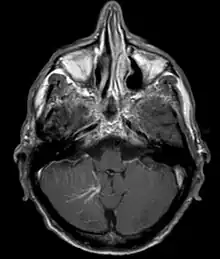

| Developmental venous anomaly in the cerebellum seen on axial contrast-enhanced T1 weighted MRI | |

A developmental venous anomaly (DVA, formerly known as venous angioma) is a congenital variant of the cerebral venous drainage. On imaging it is seen as a number of small deep parenchymal veins converging toward a larger collecting vein.

DVA can be characterized by the caput medusae sign of veins, which drains into a larger vein. The drains will either drain into a dural venous sinus or into a deep ependymal vein. It appears to look like a palm tree.[1]